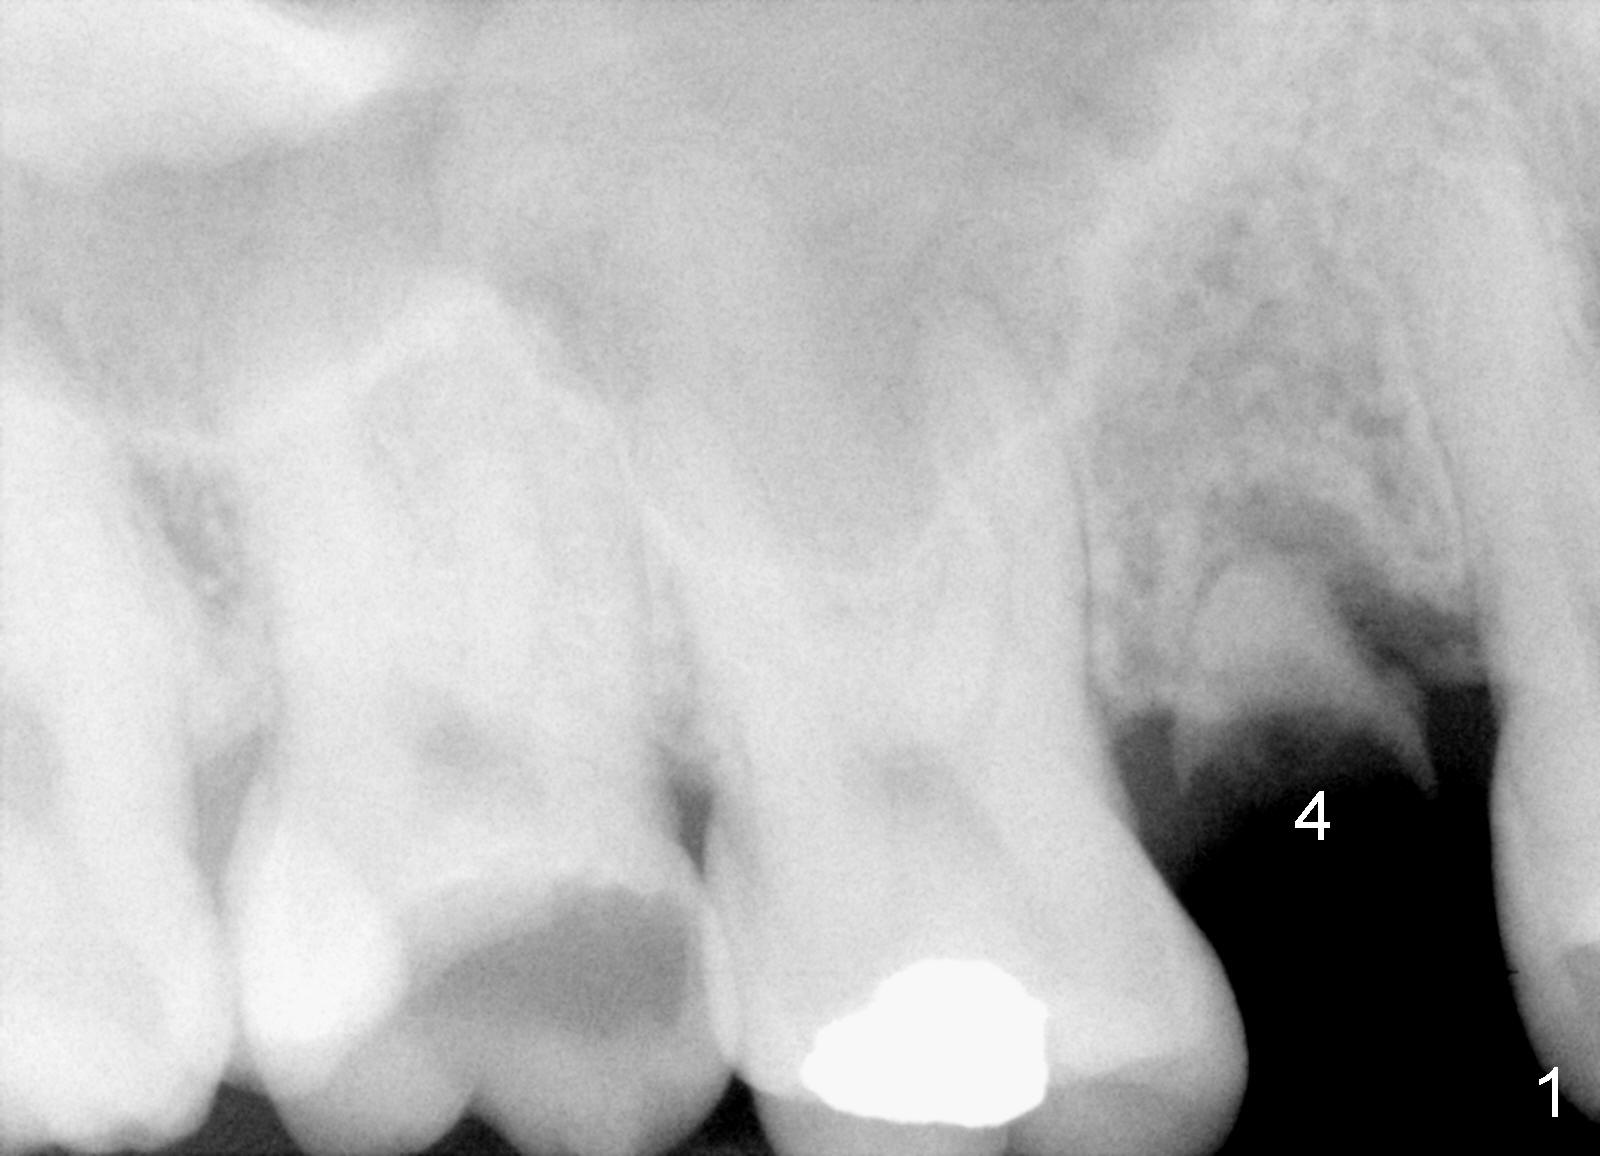

The tooth #4 was removed from a 41-year-old man (Fig.1). Fig.2 was taken 1 year and 7 months post extraction. Osteotomes (Fig.3,4) were used to create osteotomy (7 yr 9 m post ext). A 4x14 mm implant was placed below the sinus floor with insertion torque > 60 Ncm (Fig.5). The surgery was flapless (Fig.6). No antibiotic was taken pre- and post-op. The implant was found to be tender and loose. It was removed without bone graft.